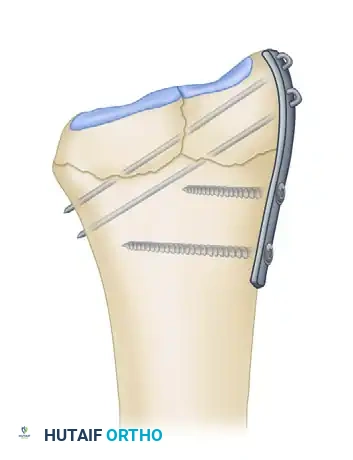

DISTRACTION PLATE FIXATION (DORSAL SPANNING PLATE)

As an alternative to external fixation for highly comminuted fractures of the distal radius, Burke and Singer described the use of a distraction plate as an internal fixator. This technique was later modified and popularized by Ruch et al., who reported good-to-excellent outcomes in 90% of patients.

The distraction plate is applied to the dorsal surface of the hand, wrist, and distal forearm. By spanning the radiocarpal joint, it relies on the principle of ligamentotaxis to restore radial length and alignment. Because the implant is entirely internal, external pin site problems are avoided, and the plate can remain in place as long as necessary for union (typically 12 to 16 weeks). Furthermore, secondary bone grafting procedures are performed much more easily without the physical obstruction of an overlying external fixator frame.

4. Plate Tunneling:

Select a 12- to 16-hole, 3.5-mm dynamic compression plate or dedicated spanning plate. Pass the plate from the distal incision in a proximal direction. The plate must glide through the plane between the extensor tendons (specifically the fourth dorsal compartment) and the joint capsule/periosteum. Mobilize the extensor tendons as necessary to ensure the plate sits flat against the bone.

5. Distal Fixation:

Secure the plate to the long finger metacarpal shaft using three bicortical 3.5-mm screws.

6. Distraction and Proximal Fixation:

Under fluoroscopic guidance, apply longitudinal distal traction to the fingers to obtain normal radial length and restore the radiocarpal joint space via ligamentotaxis. With the hand held in approximately 60 degrees of supination, secure the plate to the proximal radius with a bone clamp. Confirm that full rotation of the forearm is possible without impingement. Once confirmed, secure the plate to the radial shaft with three bicortical 3.5-mm screws.

7. Adjunctive Fixation and Grafting:

* Reduce and fix any large diaphyseal fragments to the shaft with interfragmentary lag screws if possible.

* Through the middle incision, elevate the depressed lunate fossa.

* Insert a 3.5-mm screw through the plate and under the elevated lunate fossa to serve as a subchondral buttress.

* Percutaneously pin other intra-articular fragments using Kirschner wires to stabilize the articular surface.

* Place bone graft (autograft, allograft, or synthetic substitute) into the metaphyseal voids through the middle incision.